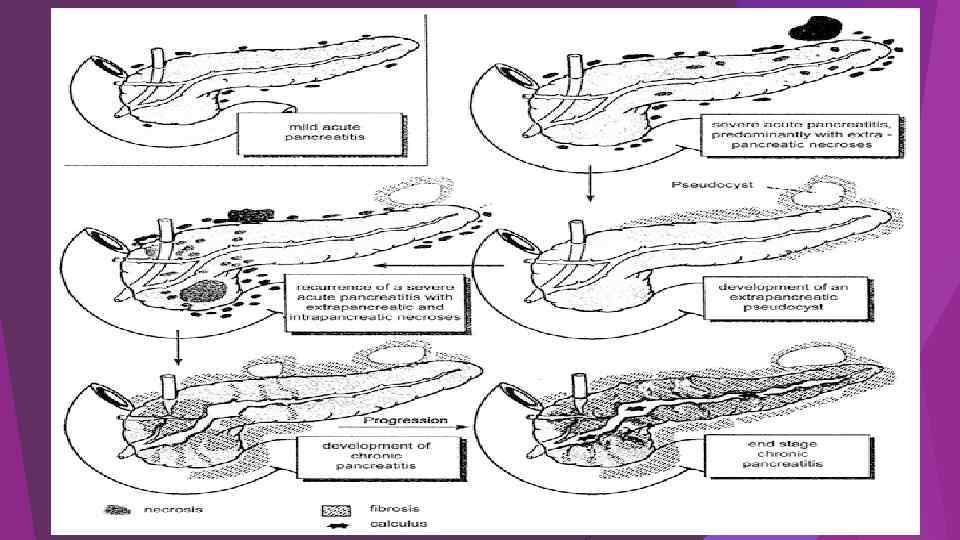

Острый панкреатит – это воспалительно-некротическое поражение поджелудочной железы, в основе которого лежат процессы ферментного аутолиза ( «самопереваривания» ) панкреатоцитов с последующим развитием некроза, дегенерации железы и возможным присоединением вторичной инфекции. Клиническая классификация острого панкреатита 1. Отечный (интерстициальный) панкреатит. 2. Некротический (панкреонекроз) стерильный панкреатит : по характеру некротического поражения: жировой, геморрагический, смешанный; по распространенности поражения: мелкоочаговый, крупноочаговый, субтотальный, тотальный; по локализации: с поражением головки, тела, хвоста, всех отделов поджелудочной железы. 3. Некротический (панкреонекроз) инфицированный панкреатит.

Острый панкреатит – это воспалительно-некротическое поражение поджелудочной железы, в основе которого лежат процессы ферментного аутолиза ( «самопереваривания» ) панкреатоцитов с последующим развитием некроза, дегенерации железы и возможным присоединением вторичной инфекции. Клиническая классификация острого панкреатита 1. Отечный (интерстициальный) панкреатит. 2. Некротический (панкреонекроз) стерильный панкреатит : по характеру некротического поражения: жировой, геморрагический, смешанный; по распространенности поражения: мелкоочаговый, крупноочаговый, субтотальный, тотальный; по локализации: с поражением головки, тела, хвоста, всех отделов поджелудочной железы. 3. Некротический (панкреонекроз) инфицированный панкреатит.

Фазы течения острого панкреатита 1. фаза энзимной токсемии ( 7 -10 суток от начала заболевания) 2. фаза проявлений полиорганной недостаточности ( с 310 суток) 3. фаза деструктивных осложнений ( с 7 -10 суток) - период асептических деструктивных осложнений - период гнойных деструктивных осложнений ( 2 -3 неделя заболевания)

Фазы течения острого панкреатита 1. фаза энзимной токсемии ( 7 -10 суток от начала заболевания) 2. фаза проявлений полиорганной недостаточности ( с 310 суток) 3. фаза деструктивных осложнений ( с 7 -10 суток) - период асептических деструктивных осложнений - период гнойных деструктивных осложнений ( 2 -3 неделя заболевания)

Осложнения острого панкреатита 1. Перипанкреатический инфильтрат. 2. Инфицированный панкреонекроз. 3. Панкреатогенный абсцесс. 4. Псевдокиста: стерильная, инфицированная 5. Панкреатогенный ферментативный (абактериальный) асцит-перитонит. 6. Инфицированный (гнойный) перитонит. 7. Септическая флегмона забрюшинной клетчатки: парапанкреатической, параколической, паранефральной, тазовой. 8. Механическая желтуха. 9. Внутренние и наружные дигестивные свищи.

Осложнения острого панкреатита 1. Перипанкреатический инфильтрат. 2. Инфицированный панкреонекроз. 3. Панкреатогенный абсцесс. 4. Псевдокиста: стерильная, инфицированная 5. Панкреатогенный ферментативный (абактериальный) асцит-перитонит. 6. Инфицированный (гнойный) перитонит. 7. Септическая флегмона забрюшинной клетчатки: парапанкреатической, параколической, паранефральной, тазовой. 8. Механическая желтуха. 9. Внутренние и наружные дигестивные свищи.